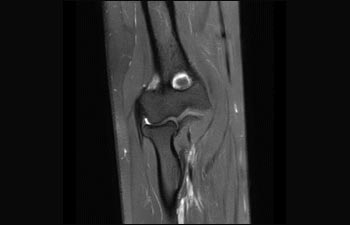

La Sra. Silvia Schiffer, directora y radióloga experta en la clínica Radiologie Schiffer, en Alemania, comparte sus experiencias con el sistema de RM Prodiva 1.5T.

Conozca la opinión de los primeros usuarios de Ingenia Prodiva 1.5T acerca de sus experiencias con el sistema y cómo influye este en su centro de diagnóstico por imagen.

1De acuerdo con un estudio interno en el que se compara el flujo de trabajo con el equipo de RM Achieva. 2 ComforTone estará disponible con Prodiva 1.5T en el cuarto trimestre de 2017 3 De acuerdo con un estudio interno donde se compara el flujo de trabajo en una combinación de aplicaciones cerebrales, musculoesqueléticas, de columna y de cuerpo con el equipo de RM Achieva 4 La operación normal se define como una adquisición típica realizada con suministro continuo de electricidad, así como de refrigeración del imán, sin incluir las actividades de servicio 5 En función del contrato y de la disponibilidad local 6 Con "otros equipos de RM" nos referimos a equipos de RM de 1,5 T de 60 cm para exámenes de cuerpo entero